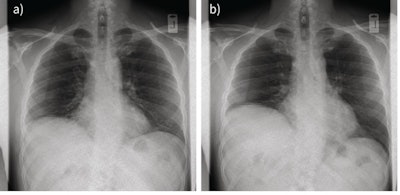

Two still images from a dynamic chest radiography sequence showing paradoxical movement of the paralyzed right hemidiaphragm from (a) rest to (b) end sniff maneuver. Image courtesy of ERJ Open Research.In addition, the time taken for preparation, patient instruction, and image acquisition was approximately five minutes per patient, which is comparable to standard chest x-rays, the authors noted.